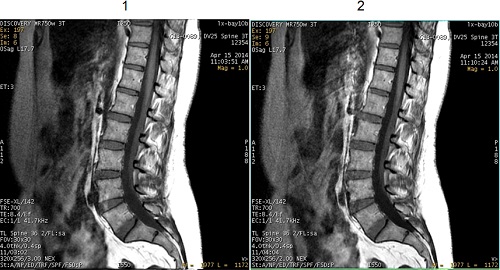

FSE T1 Optimization

Use FSE T1 Optimization to optimize the T1 contrast in brain and spine images acquired with 2D FSE T1 pulse sequences.

| Number | Description |

|---|---|

| 1 | FSE T1-weighted image |

| 2 | FSE T1-weighted image with FSE T1 Optimization |

The User CV applies a +90° RF pulse at the end of the echo train that results in a darker signal from fluids thus improving T1 contrast when compared to a conventional FSE sequence. In addition, the scan time may be decreased when compared to a SE T1 sequence.